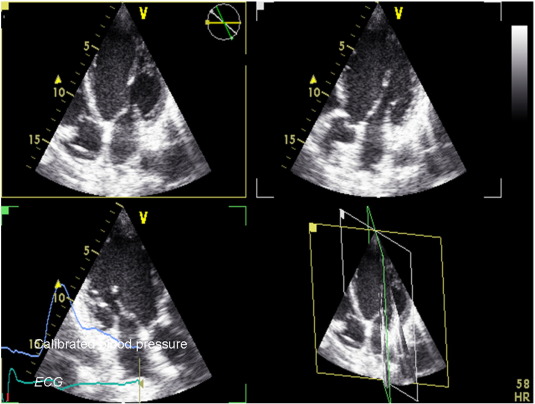

Pacing was initiated at spontaneous heart rate, or at fixed 70 beats/min in those patients with permanent atrial fibrillation or atrioventricular block, with 2 subsequent steps at 100 and 120 beats/min lasting for approximately 2 min. The other pacing mode was used to repeat the same sequence after a few minutes delay. During each step, continuous blood pressure measurements (taken with the right arm) were recorded using a digital photoplethysmography device capable of providing accurate beat-to-beat systolic and diastolic values (Finapress, Omeda 2300, Monitoring Systems) [15]. Continuous blood pressure signals were also visible on the screen of the echo machine (Fig. 1). After the protocol was completed, the device was reprogrammed in DDD-CRT mode with a fixed optimized AV and VV interval, with scheduled clinical follow-ups and device checks.

Fig. 1

Fig. 1.

Methodology adopted for the study. Ventricular volumes were obtained using real-time 3 apical simultaneous longitudinal planes and then by manually tracing the endocardial border with in-built software. Calibrated continuous blood pressure, together with ECG signal, was also available on the screen of the echo machine.